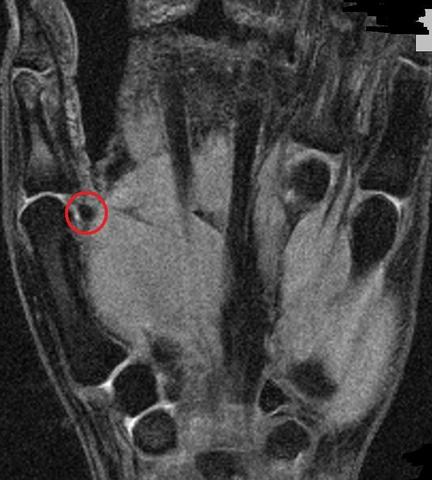

Aufgrund eines Unfalles habe ich mir im linken Vorderfuss das Sesambein gebrochen Nach fast einem Jahr habe ich nach wie vor starke Schmerzen im Vorderfuss Bei Belastung zB nach dem Laufen deutlich mehr Nach dem MRT ist zu sehen, dass dieser Knochen nach wie vor entzweit ist, wobei ein Teil davon dunkel ist Laut Aussage des beh. Issuu is a digital publishing platform that makes it simple to publish magazines, catalogs, newspapers, books, and more online Easily share your publications and get them in front of Issuu’s. Sesambein gebrochen Hallo, ich brauche für meine Lauffreundin dringend mal jemanden, der Erfahrung mit der operativen Entfernung des Sesambeins hat Sie pausiert deswegen seit Wochen und andere Therapien helfen nicht Wenn ich es richtig verstanden habe, befindet sich im Knochen ein Ödem, welches Schmerzen beim Laufen verursacht.